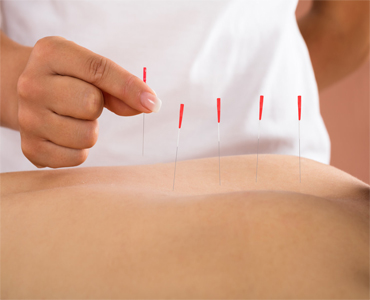

Dry Needling

Dry needling is a treatment that healthcare providers use for pain and movement issues associated with myofascial trigger points. With this technique, a provider inserts thin needles into or near your trigger points...